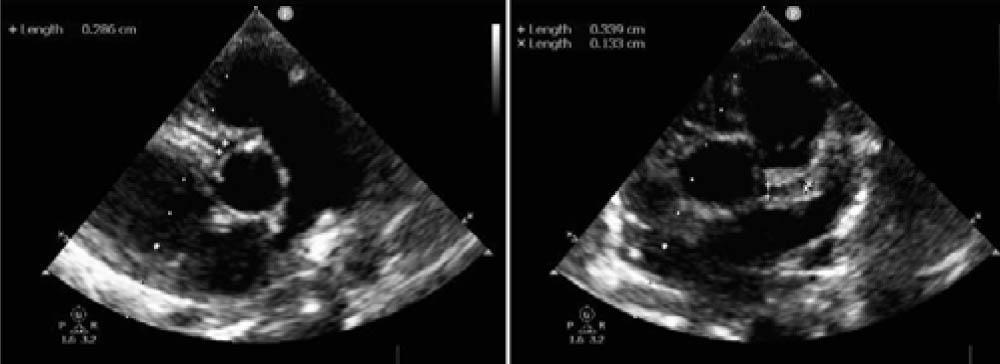

Figure 2

Figure 3